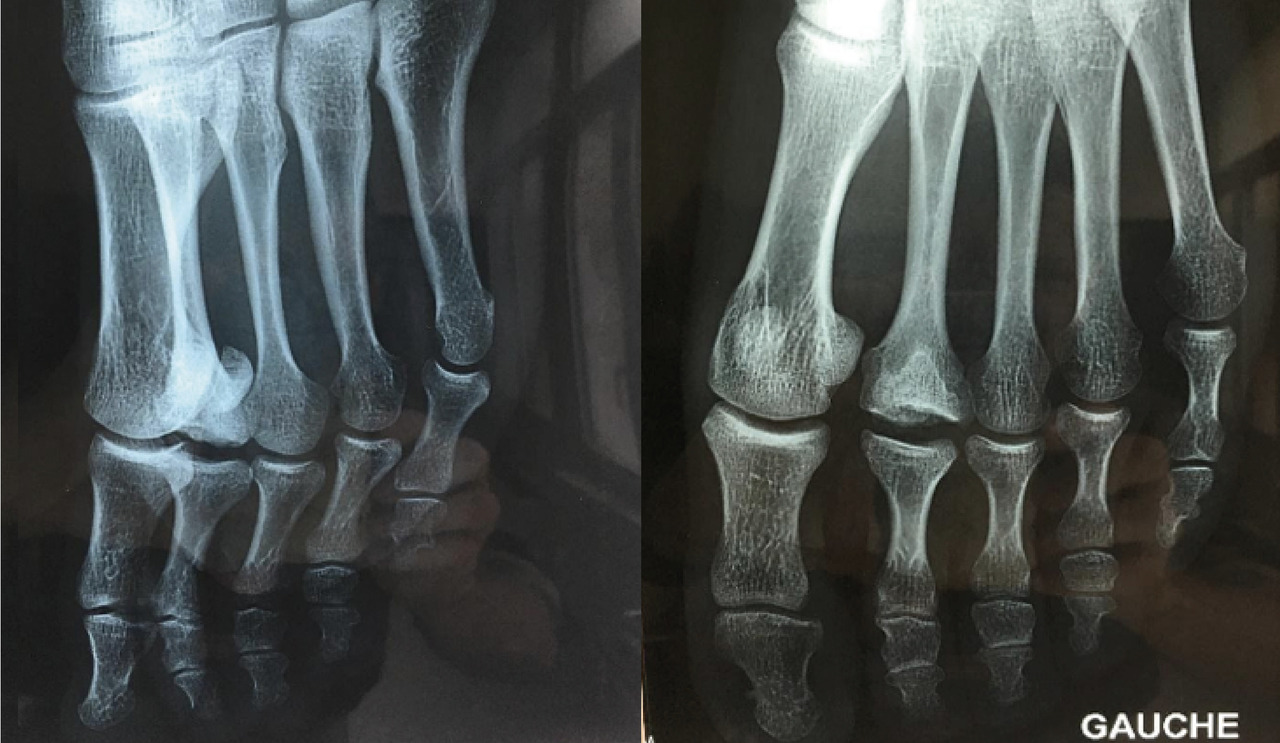

L’examen met en évidence une tuméfaction solide et une douleur à la palpation au niveau de la tête du 2e méta­tarsien. La flexion des orteils dévoile une dépression au niveau de l’articulation métatarsophalangienne, laissant apparaître très nettement le tendon extenseur qui semble en suspension (fig. 1).